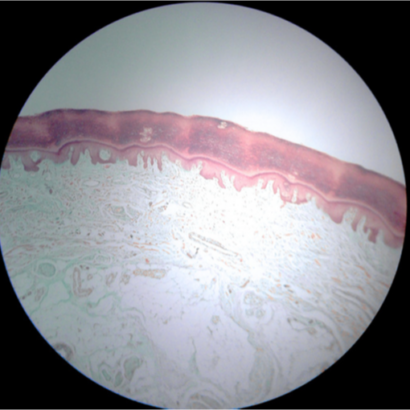

Infections in complex wounds often lead to prolonged treatment, hospital stays, and long-term complications. Supported by the Marie Skłodowska-Curie Actions programme, the INTROS project is tackling this head-on by training a new generation of scientists to develop smart materials and tools for early diagnosis and infection prevention. Through a multidisciplinary doctoral network, INTROS is advancing nano- and micro-scale delivery systems, hydrogel-based patches, and biodegradable sensors that detect infection and deliver targeted therapies. These solutions aim to reduce inflammation, support healing, and minimise scarring. The project also prioritises scalable manufacturing and real-world testing in lab and ex vivo wound models. By combining cutting-edge science with hands-on industry training, INTROS is transforming the way we treat wounds.